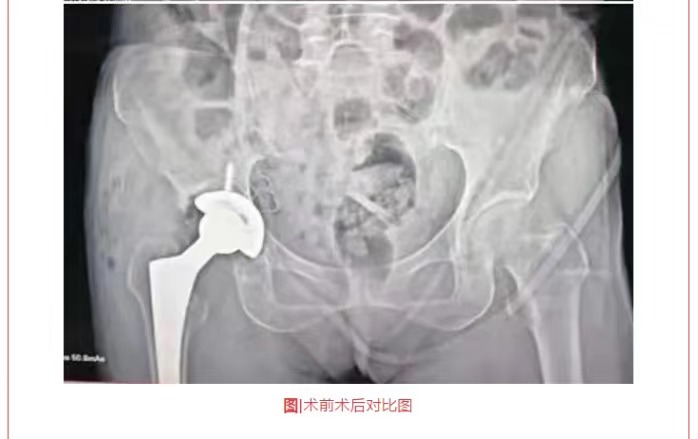

熱烈祝賀穗康長(zhǎng)貞醫(yī)院成功完成兩例全髖關(guān)節(jié)置換術(shù)

摘要:惠東穗康長(zhǎng)貞醫(yī)院一直以來(lái)本著“生命至上、以人為本”的職業(yè)理念,以“服務(wù)社會(huì)、取信于民”為追求,在黃寶壬董事和陳啟海院長(zhǎng)的領(lǐng)導(dǎo)下,不忘初心,砥礪前行,不斷提高技術(shù)服務(wù)、持續(xù)加強(qiáng)醫(yī)療服務(wù),以救死扶傷為本職,還廣大市民一份健康。